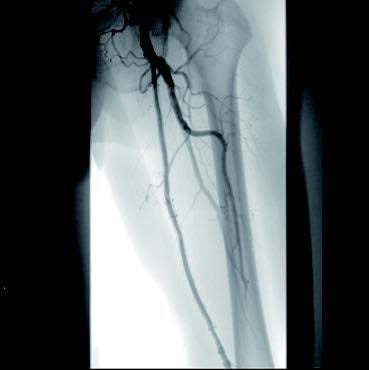

[背景] 左間欠性跛行で14年前に左SFAにベアナイチノールステント6 mm × 120 mm 2本が留置されている(図1)。約7年前に左間欠性跛行が増悪し、来院。外来での超音波検査でベアステントの完全閉塞を認めた(図2)。高度の跛行があり、再治療を実施した。